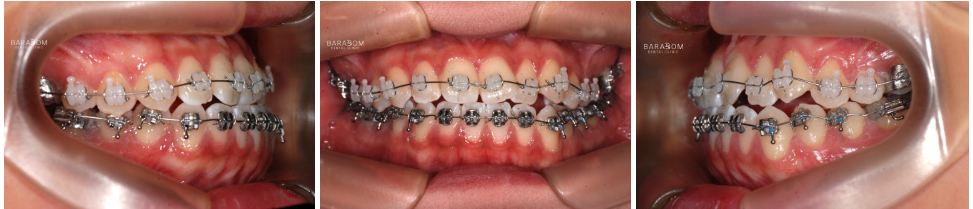

안모의 문제뿐만 아니라

부정교합도 함께 관찰됩니다.

안모와 동일하게 좌우

다른 문제를 가지고 있죠.

1️⃣좌측은 일부 치아가

거꾸로 물리는 반대교합 양상이

확인됩니다.

이런 경우 불안정한 힘이

치아에 가해져 파절로

이어질 수 있습니다.

2️⃣우측은 앞니의 끝부분 즉 절단연끼리

맞물리고 있는데요,

이를 절단 교합이라 부릅니다.

이렇게 맞물리는 양상 역시

힘을 고르게 분산시키기 어려워

절단연 파절로 이어질 수 있으며

턱관절에 안정을 찾기 어렵고

과도한 긴장 상태를 유지하게 됩니다.

윗니가 아랫니를 덮는 것이

정상적인데, 이 경우

정반대로 아래가 위를 덮는 듯한

모습이 관찰됩니다.

✅더불어 구치부의 맞물림 역시

올바르지 못한데요,

윗턱 성장 부전이 있어

골격성 3급으로 진단됩니다.

더불어 아랫턱이 좌측으로 변위되며

비대칭을 이루고 있습니다.

장치(브라켓)를 달고

변위된 치아를 제 자리로 이동시킴과 동시에

아랫치열을 후방으로 밀기 시작합니다.

그래야 안정적인 교합을

유도할 수 있기 때문이죠.